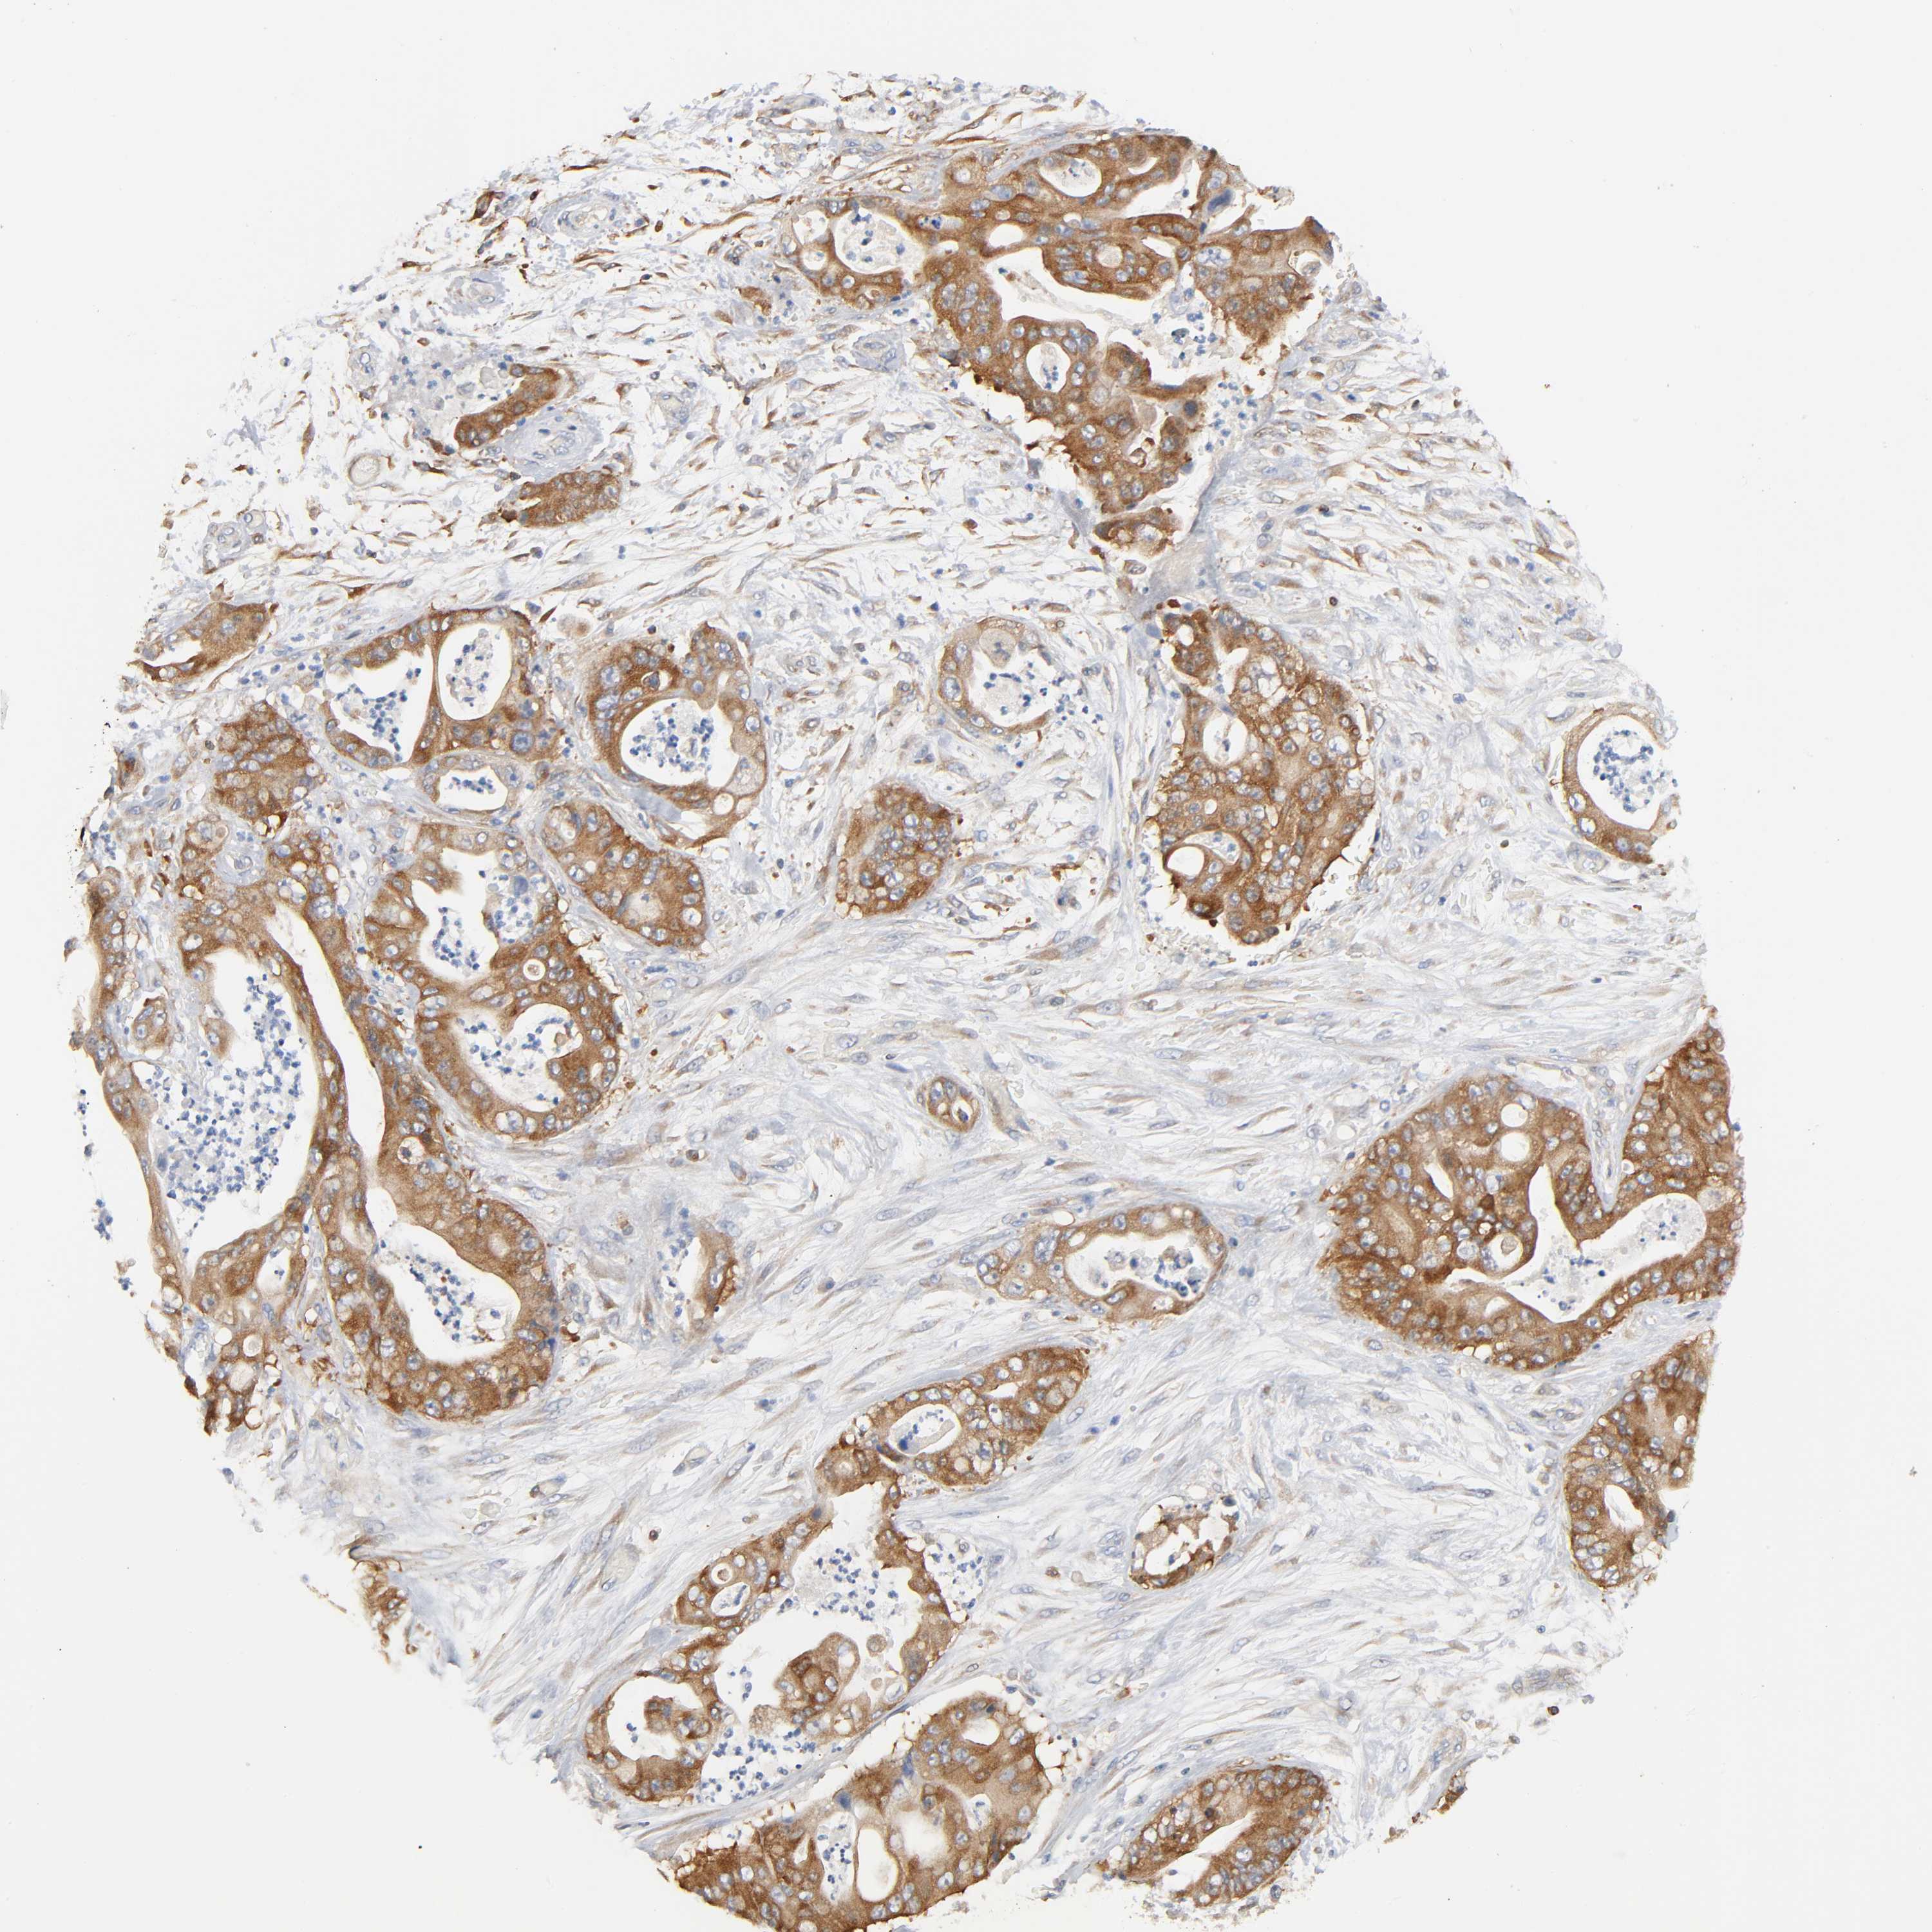

STOMACH CANCER - Protein expressioni

A mouse-over function shows sample information and annotation data. Click on an image to view it in a full screen mode. Samples can be filtered based on level of antibody staining by selecting one or several of the following categories: high, medium, low and not detected. The assay and annotation is described here.

Note that samples used for immunohistochemistry by the Human Protein Atlas do not correspond to samples in the TCGA dataset.

Antibody stainingi

Antibody staining in the annotated cell types in the current human tissue is reported as not detected, low, medium, or high, based on conventional immunohistochemistry profiling in selected tissues. This score is based on the combination of the staining intensity and fraction of stained cells.

Each image is clickable and will lead to virtual microscopy that enables deeper exploration of all samples and also displays staining intensity scores, fraction scores and subcellular localization as well as patient and tissue information for each sample.

Antibody HPA003894

Antibody HPA005437

Antibody CAB001945

Staining

High

Medium

Low

Not detected

Adenocarcinoma, NOS

Adenocarcinoma, High grade